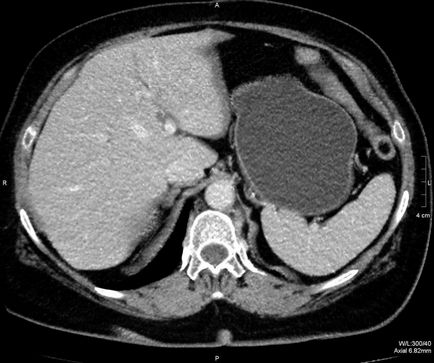

ultrahang diagnosztika

A mai orvostudomány lehetővé teszi, hogy csinál egy ultrahang fotót vese ciszták, és meghatározza a daganat kapszula található, a természet megbetegítő hatása van a szervezetben, valamint az összeg által érintett szövet.

Mivel a gyenge megnyilvánulása tünetek korai szakaszában a fejlődés, vese ciszta látható csak az ultrahang-vizsgálat vagy egy tomográfiás vizsgálat.

A tumor a fejlesztési folyamatban képesek behatolni a mélyebb rétegek a veseszövet és provokál duzzanat és a kár a szomszédos szervekhez. Ez a folyamat látható a fekete pontok formájában az ultrahang képeket.

Külső ciszták, amelyek a fedélhez csatlakoztatott veseszövet, lehet szkennelt ultrahanggal több szürke foltok szabálytalan alakú egyenes élek.